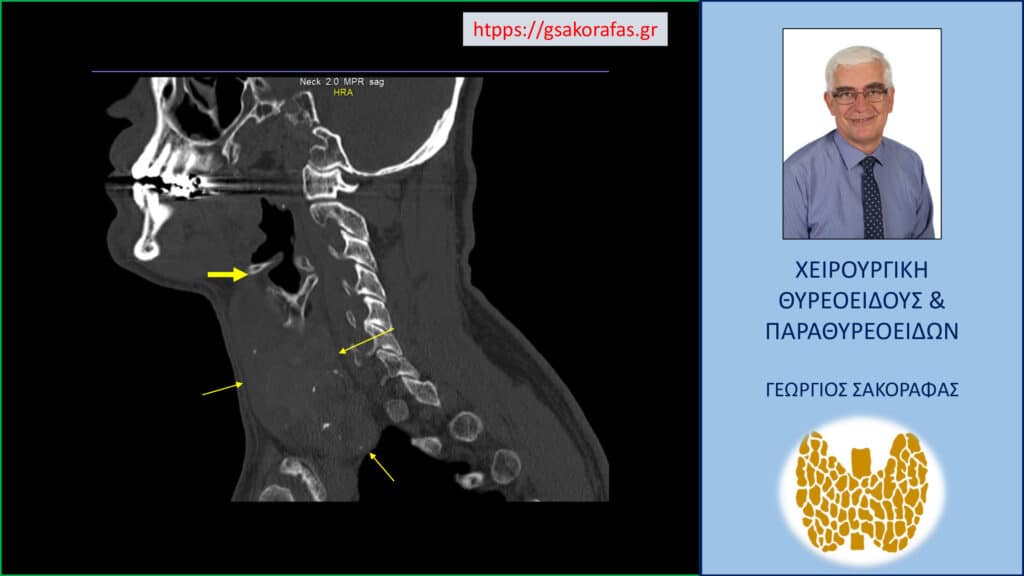

Σε επιλεγμένες περιπτώσεις μπορεί να χρειαστεί απεικονιστικός έλεγχος με αξονική ή μαγνητική τομογραφία, κυρίως σε ασθενείς με ευμεγέθη βρογχοκήλη (δηλαδή με μεγάλου βαθμού διόγκωση του θυρεοειδούς) που καταδύεται στο μεσοθωράκιο, προκειμένου να προσδιοριστεί το βάθος στο οποίο επεκτείνονται εντός της θωρακικής κοιλότητας. Η πληροφορία αυτή είναι βασική για τον σωστό σχεδιασμό της επέμβασης.